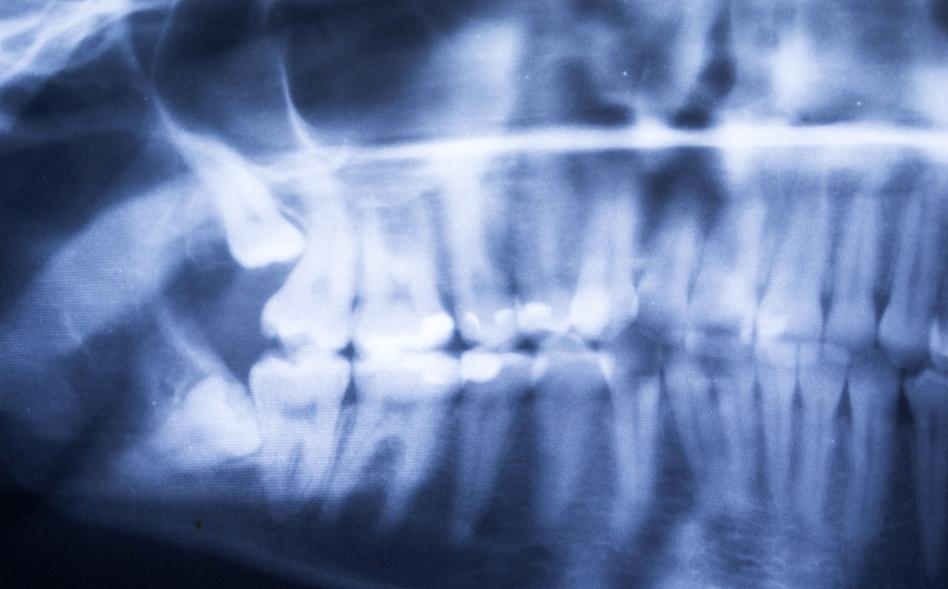

If you are experiencing pain, our team will perform a thorough examination, often including X-rays, to determine the position of your wisdom teeth and whether removal is the best option. In many cases, extraction is recommended to prevent ongoing pain, infection, or damage to surrounding teeth.